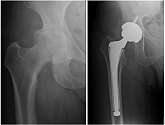

Hüftendoprothetik

In den späten Stadien der Arthrose des Hüftgelenks, mediale Frakturen des Schenkelhalses in der älteren Altersgruppe, ist die einzige Möglichkeit, sich zu erholen, das betroffene Gelenk durch eine künstliche Gelenkarthroplastik zu ersetzen.

Diese Methode ermöglicht es Ihnen, die Gliedmaße, das volle Volumen der Bewegungen im betroffenen Gelenk, zurückzugeben, um von ständigem Schmerz und Knirschen während der Bewegungen zu sparen und folglich den Patienten zu einem vollen aktiven Leben zurückzubringen.

Im Folgenden werden Röntgenaufnahmen und Fotografien vorgestellt, die das Ausmaß der Bewegung im betroffenen Gelenk vor und nach der Operation zeigen.